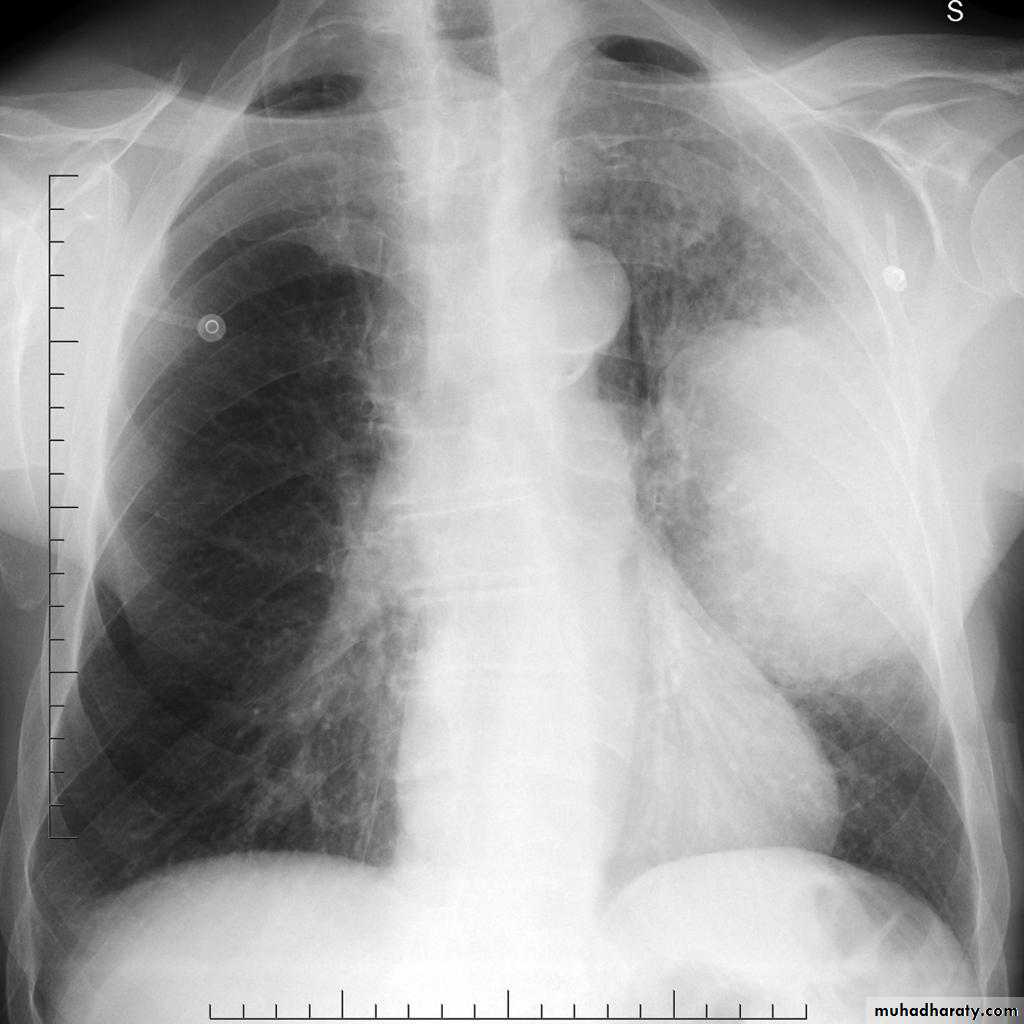

Metastisis to Lung (canon ball appearance)

CXR of adult, PA view shows Bilateral rounded radioopaque nodules of multiple sizes distributed all over both lung fields( Cannon ball appearance)